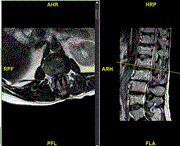

Case series of intradural disc in recurrence of lumbar disc prolapse

Bashar Alhani and others

Journal of Surgical Case Reports, Volume 2021, Issue 2, February 2021, rjaa611, https://doi.org/10.1093/jscr/rjaa611